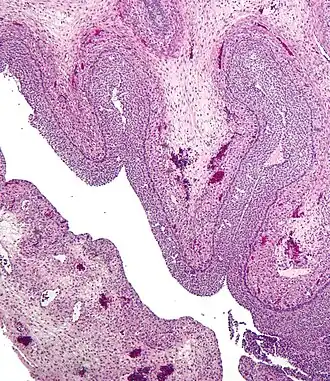

Human ovary with fully developed corpus luteum -

Luteinized follicular cyst. H&E stain.